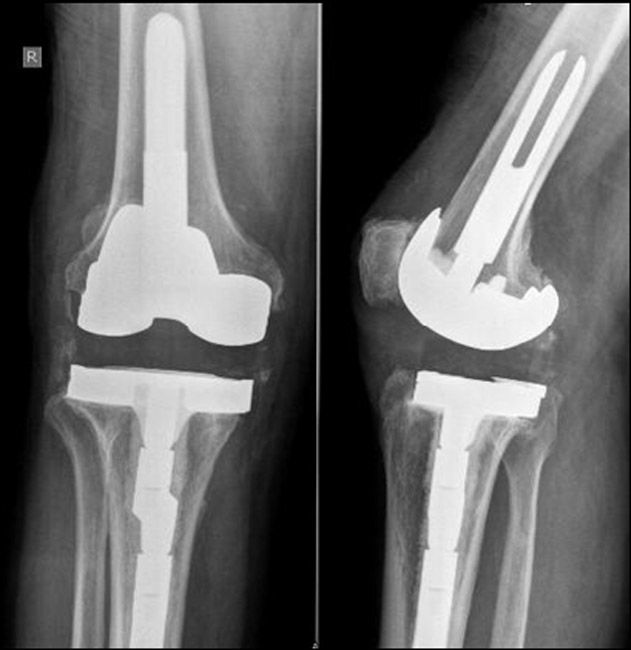

Background Prosthetic joint infection PJI of total hip THA or total knee arthroplasty TKA after dental procedures is uncommon and antibiotic prophylaxis remains controversial. Fevers night sweats and chills.

Symptoms of hip replacement infection after dental work. This is problematic in places like the gut gastrointestinal system where an altered microbiome can cause diarrhea abdominal pain malabsorption of nutrients and a host of other unwanted symptoms. Symptoms of Joint Infection. A small percentage of patients undergoing hip or knee replacement roughly about 1 in 100 may develop an infection after the operation.

Chronic infections may have very subtle presentations. One of the risk factors for developing an infection after a dental procedure is having artificial hardware in ones body. There is an estimated 05 to 1 risk of an infection following a hip replacement.

Infection after dental work Dental work from cleaning to root canals may cause bleeding and an opening where bacteria can enter the body. Multivariate-adjusted analyses confirmed that there was no association between the incidence of PJI and prophylactic antibiotics. Joint replacement infections may occur in the wound or deep around the artificial implants.

CONCLUSIONS The risk of PJI is not increased following dental procedure in patients with hip or knee replacement and is unaffected by antibiotic prophylaxis. There are many studies that examine the risks of PJIs with dental work. Joint replacement infections can even occur years after.

Developing an infection in and around a total hip or knee replacement is one of the most catastrophic complications that can occur. Increased stiffness and pain in a normally well-functioning joint. Symptoms of artificial joint infection.